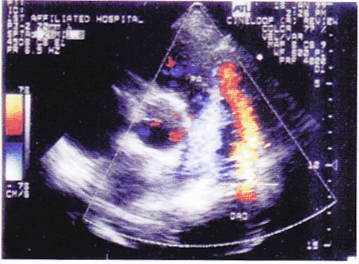

如图大动脉短轴所示,该病例最有可能的诊断为()。

A、肺动脉内径增宽

B、动脉导管未闭

C、肺动脉瓣狭窄

D、肺动脉瓣关闭不全

E、右心室流出道狭窄

正确答案:

B